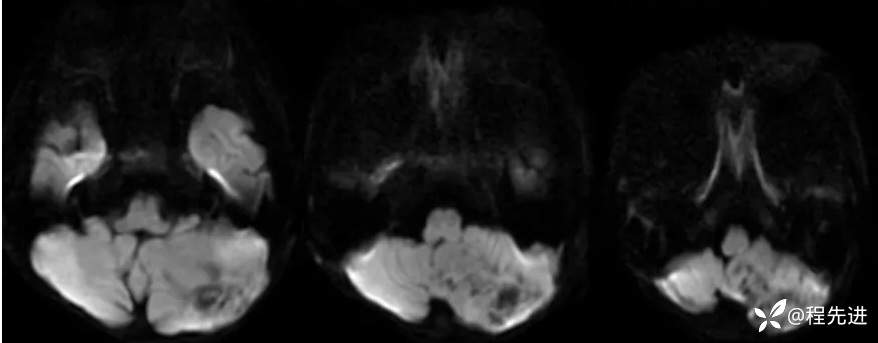

【患者信息】:男,6岁

【主诉】:查体发现左侧小脑半球占位3个月

【现病史及既往史】:患者3个月前因鼻塞至外院就诊,行头颅CT检查偶然发现颅内占位

【检查】